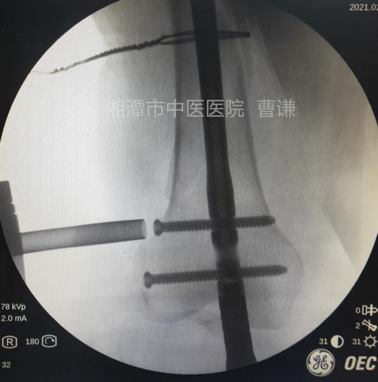

在远折端依前法再置入一根钢丝进行捆扎复位,因担心过度拧紧导致钢丝断裂,没有强求骨折解剖复位。

追求完美者可以将钢丝再拧紧一些,复位将更漂亮。

扩髓后沿导针置入髓内钉,注意尾端不要突出髁间窝,髓内钉尖端应置于小转子水平。

安装瞄准器后分别置入远端锁钉及近端锁钉,透视锁定良好。

透视侧位骨折对位对线良好,锁钉位置良好。